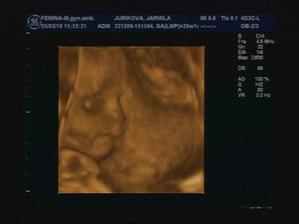

17.5.2010 - 32+5tt, máme 1847g, narástli sme. :DD